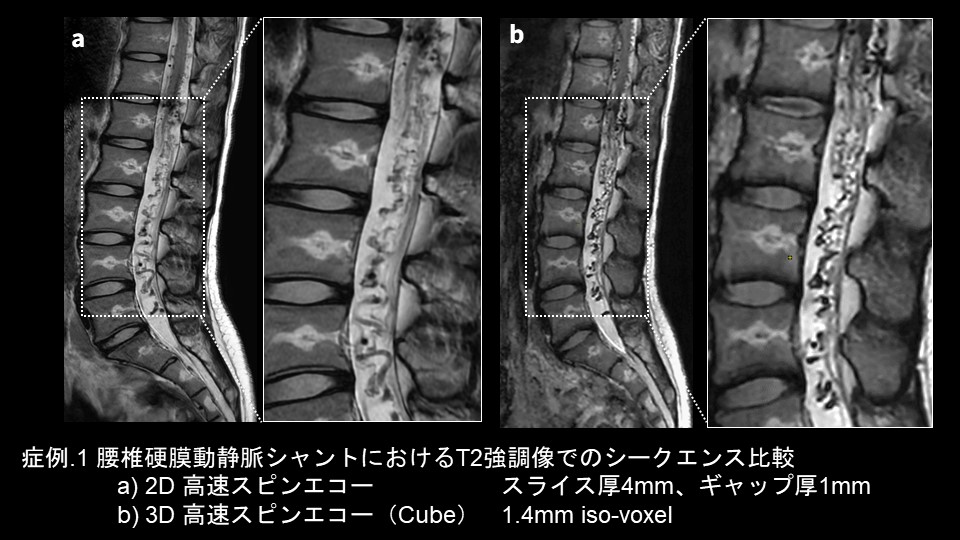

・症例1

脊椎領域の硬膜動静脈シャントの症例です。スライス厚4mm・ギャップ1mmでの撮像した2D 高速スピンエコー法によるT2強調像と、1.4mmのiso-voxelで撮像した3D 高速スピンエコーシーケンスであるT2 cubeを提示しています。2D 高速スピンエコーで得られたT2強調像で、蛇行した静脈の拡張が確認できます(症例.1-a)。一方、3D 高速スピンエコーのCubeで撮像した1.4mm iso-voxelの矢状断像は、部分容積効果が低減されているため、従来のT2強調矢状断像よりも拡張静脈が明瞭に描出されています(症例.1-b)。スライス厚を薄くするとノイズによる画質低減が問題となり、検査時間が限られている関係上、臨床活用が難しいという問題がありました。しかし、AIR™ Recon DLを活用することにより1.4mm厚にしても4分程度の撮像時間で済んでいるため、非常に使いやすくなりました。また等方性ボクセルで撮像することで、Multiplanar reconstruction (MPR)による多断面の再構成が可能になることで、拡張した静脈構造の詳細を把握しやすくなったこともメリットの一つです。